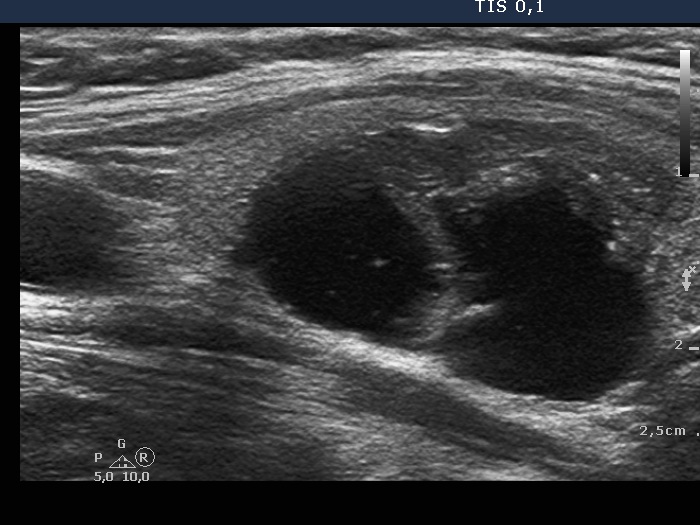

Study on 100 consecutive patients with thyroid nodule - case 042

Three years after the initial examination (ultrasonographic picture 6)

Left lobe, longitudinal scan - enlarged view. There are punctate echogenic foci within the solid area in the lower pole of the nodule.